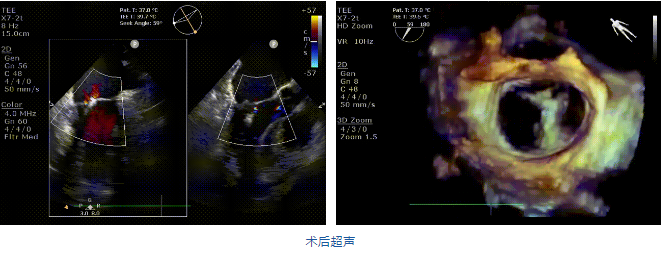

在阜外醫院潘湘斌教授團隊的支持下,手術經股靜脈-房間隔入路,采用全身麻醉插管,在TEE和DSA引導下完成房間隔穿刺。置入JensClip瓣膜夾系統后,在左房調整瓣膜夾的位置和軸向,后進入左室,在TEE引導下捕捉二尖瓣前后瓣葉,并關閉瓣膜夾。經TEE反復確認手術效果后最終鎖定并釋放瓣膜夾。術后即刻超聲顯示瓣膜夾位置穩定,功能良好,二尖瓣反流由術前4+減少至微量,手術圓滿成功。